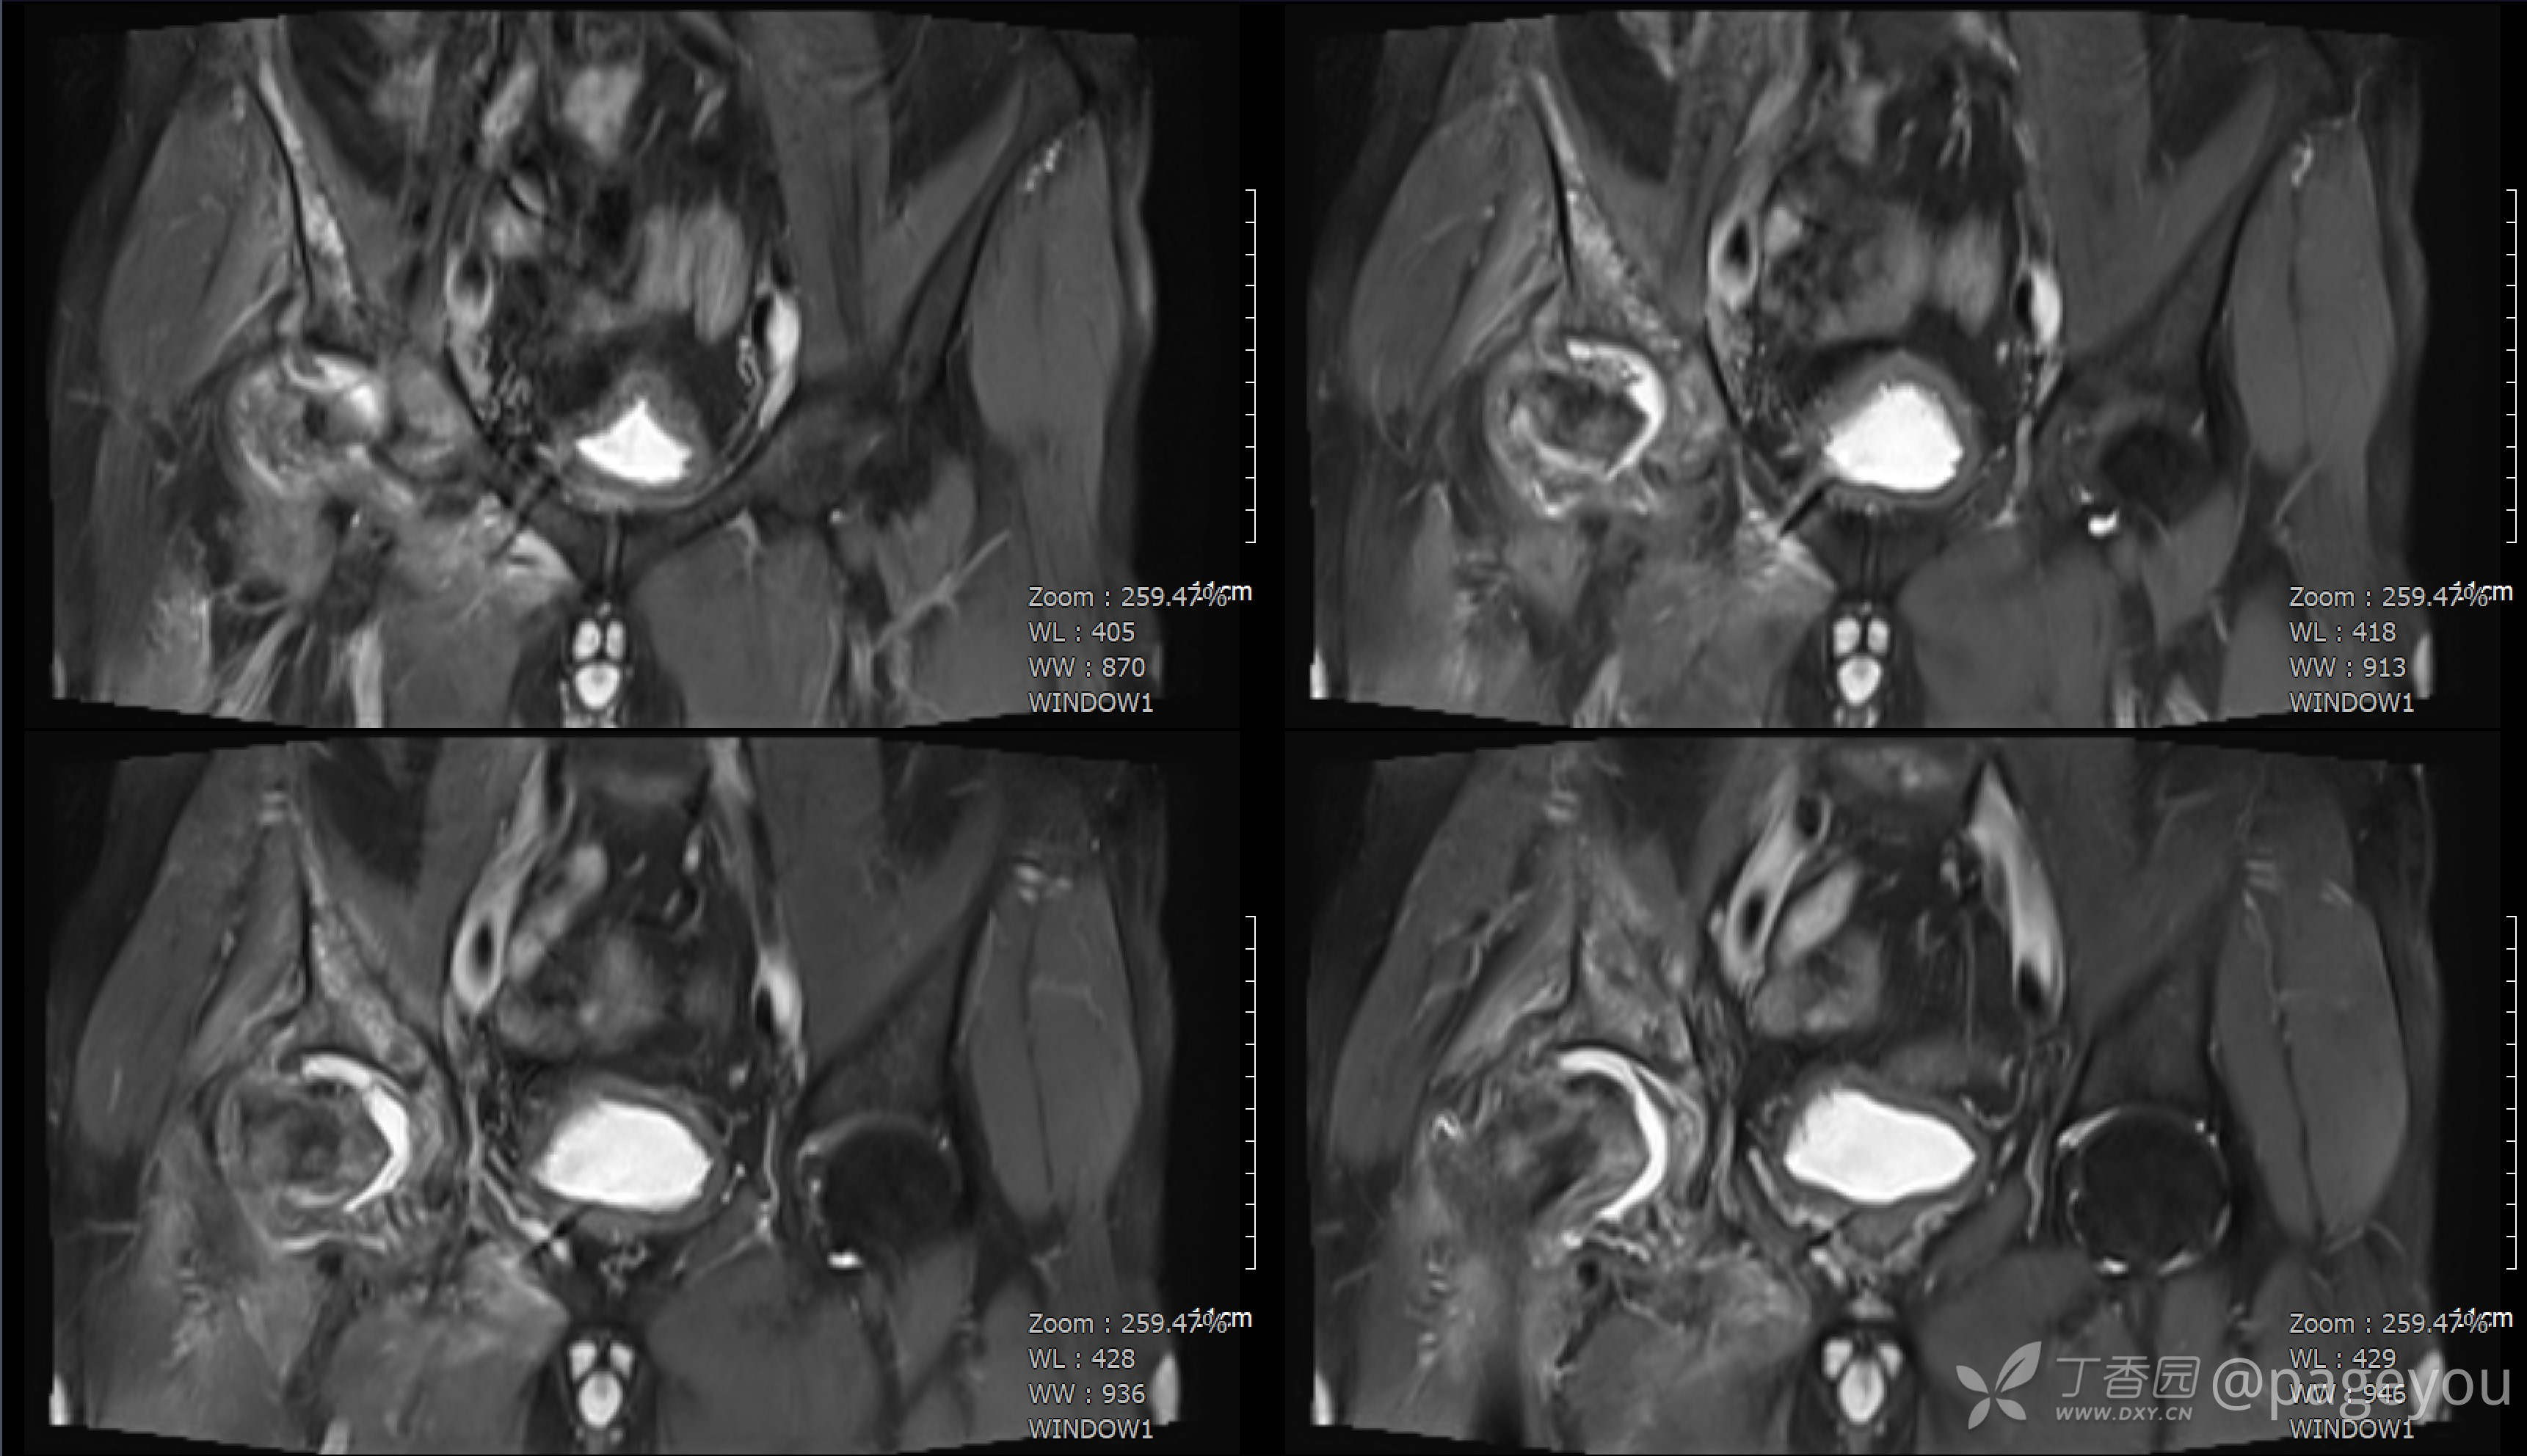

查骨盆MRI: